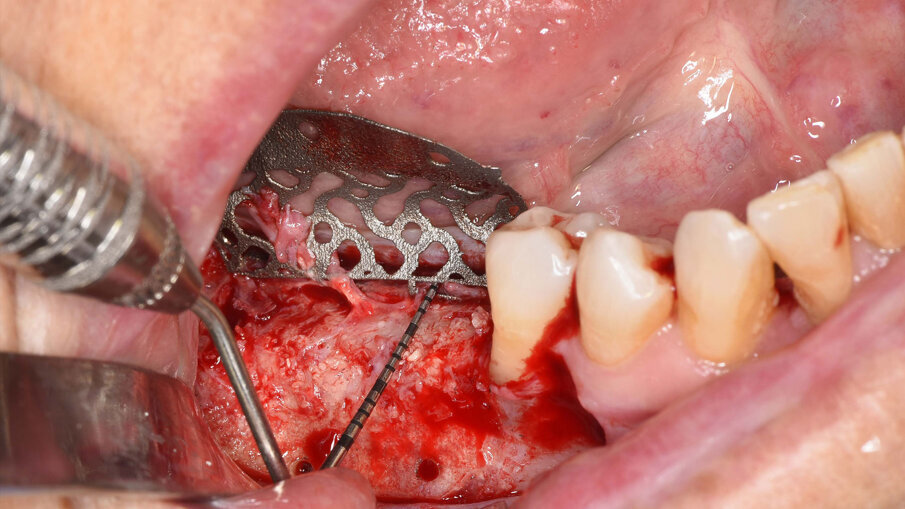

Il prelievo di osso autologo particolato è stato eseguito dal ramo mandibolare, distalmente alla zona da ricostruire mediante uno scraper (SafeScraper Twist, META). La griglia è stata provata nel sito ricevente per verificarne la congruità. Ogni residuo di tessuto connettivo è stato rimosso; per aumentare la rivascolarizzazione precoce del materiale innestato, sono state eseguite delle perforazioni della corticale ossea del sito ricevente (Figg. 3, 4). Dopo preparazione dei siti implantari, sono stati posizionati due impianti “root form” e “bone level” in zona 4.6 e 4.7 (4.1 x 8 mm; Straumann) usando una dima chirurgica. La griglia è stata quindi riempita con un mix di osso autologo ed eterologo (Geistlich Bio-Oss, Gestlich Pharma) in rapporto 1:1, è stata fissata con 3 micro-viti in titanio di 1.4 mm di diametro (MC Bio) ed è stata ricoperta con una membrana riassorbibile (Geistlich Bio-Gide, Gestlich Pharma; Figg. 5, 6). La sutura è stata eseguita per prima intenzione (Fig. 7).

Fig. 3_Fotografia che mostra la griglia sterile prima dell’inserimento nella sede da ricostruire.

Fig. 4_Visione intra-operatoria della griglia posizionata nel sito da rigenerare e che mostra il difetto osseo prima del suo riempimento.